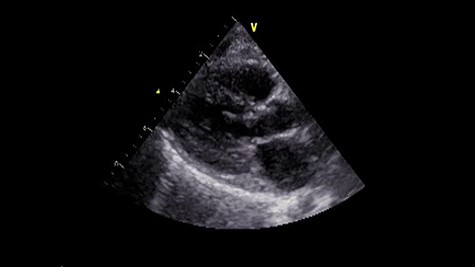

Under general anesthesia, cardiopulmonary bypass was established by ascending aortic and bicaval cannulation. After transverse aortotomy, LVOT was exposed through the aortic valve by retracting the aortic wall. The cardiac muscle hypertrophy with abnormal bundle-like cardiac muscle was observed in the LVOT, including the septal area. The hypertrophied area was scooped up by a nerve hook and cut by scalpel (Fig. 2 and Video 2). Next, the left atrium was incised and the mitral valve was exposed. The edge-to-edge technique with a suture of the A2–P2 area was performed for mitral valve reconstruction. Postoperative recovery was uneventful, and echocardiography revealed improved LVOTS with 1.7-m/s peak velocity and no MR or mitral stenosis (Fig. 3 and Video 3).

Postoperative echocardiography. The abnormal muscle band has disappeared, and the SAM of mitral valve is well controlled.